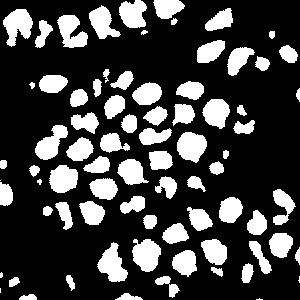

An example is shown in Fig. 2 to illustrate the masks in different rounds of self-training. The foreground nuclei annotation (green pixels) is kept unchanged during the iterations while the background area (pixels in black) grows up gradually. In the third round, the background has high accuracy and the ignored pixels (orange) are almost all nuclei.

(a) image

(b) round 1

(c) round 2

(d) round 3